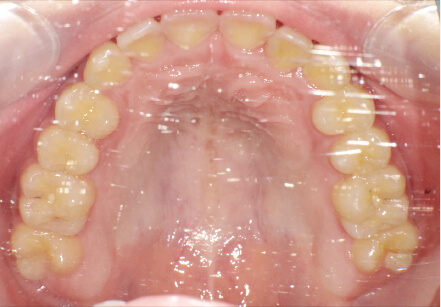

叢生の症例

19歳

女性

上の前歯が出っ歯、下の前歯がガタガタ

抜歯承諾、IPR承諾、アタッチメント承諾、ミニインプラント承諾、アレルギー有・叢生(凸凹)

全顎アライナー矯正 抜歯予定だったが抜歯リスク高いため抜歯なしでIPR量を増やす

クリアライナー

痛み・歯根吸収・歯肉退縮・虫歯・後戻り

880,000円、1年5ヶ月